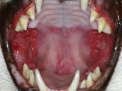

Maulhöhle einer Katze mit einer akuten Entzündung

Diese vor allem bei jüngeren und mittelalten Katzen auftretende Erkrankung, kann die Lebensqualität des Tieres massiv beeinträchtigen. Nicht nur, dass es schlechter frisst, speichelt, stark aus dem Maul riecht und Schmerzen beim Fressen hat, leiden manche Tiere auch still und ziehen sich zurück. Dies macht teilweise das Erkennen der Erkrankung durch den Tierbesitzer schwierig. Die klinische Ausprägung ist unterschiedlich und zeigt sich durch gerötetes, leicht blutendes Zahnfleisch und hochgradige, ulzerierende Entzündungen im hinteren Teil des Maules. Die vorderen Bereiche des Maules bleiben meist verschont.